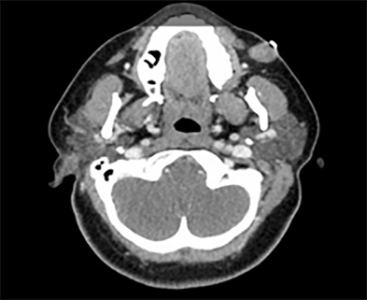

Imaging revealed a 17 mm FDG-avid well-circumscribed oval soft tissue nodule in the left buccal space within the subcutaneous soft tissues extending to the skin surface located lateral/superficial to the parotid duct suggestive of a salivary gland tumor (Fig. 2).

Fig 2